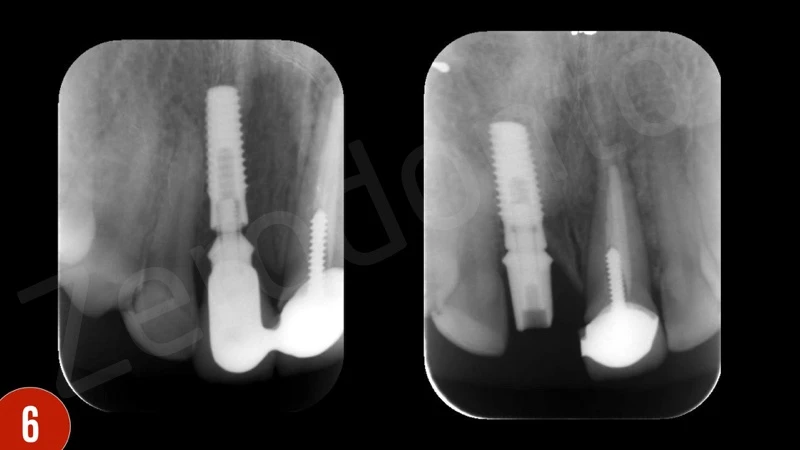

Sau khi đánh giá X-quang ban đầu, các thành phần phục hình của cấy ghép implant đã không phù hợp, răng giả được nối liền. Ngoài ra, vị trí cấy ghép quá sâu. Chảy máu khi thăm khám dương tính.

Sau khi gây tê tại chỗ, răng giả đã được cắt và loại bỏ. Sau đó, xương ổ răng vẫn hiện diện quanh implantl. Trong lần điều trị này, điều chỉnh chính xác abutment được thực hiện và xác nhận với X-quang. Khu vực cấy implant được để lành thương mô mềm. Sau 8 tuần lành thương mô mềm, phẫu thuật ghép mô liên kết (CTG) đã được lên kế hoạch với vạt bao, vạt nhú lợi xoay xiên (oblique rotated papilla flap) bằng cách sử dụng các đường rạch dưới lợi viền. Kĩ thuật chia tách tạo khả năng di động thích hợp cho vạt niêm mạc. Các phần lợi viền phía cổ được loại bỏ. CTG được lấy bằng kỹ thuật loại bỏ biểu mô. Để bù đắp thiếu hụt niêm mạc, CTG được gấp đôi và khâu bằng với vật liệu tự tiêu trước khi khâu cố định. CTG đã được cố định mặt môi, ôm lấy bề mặt abutment. Vạt niêm mạc tự do, thụ động, căng được khâu.

Sau khi nhổ răng, mô hạt đã được loại bỏ cẩn thận. Khoan xương phía khẩu cái cung cấp sự ổn định chính và đặt phục hình tạm thời. Để bảo vệ các đường cong phía môi, khoảng trống giữa bản xương phía môi và implant được ghép với xương bò khử khoáng. Phục hình tạm thời được gắn vào implant tại lực torque 15 Ncm.